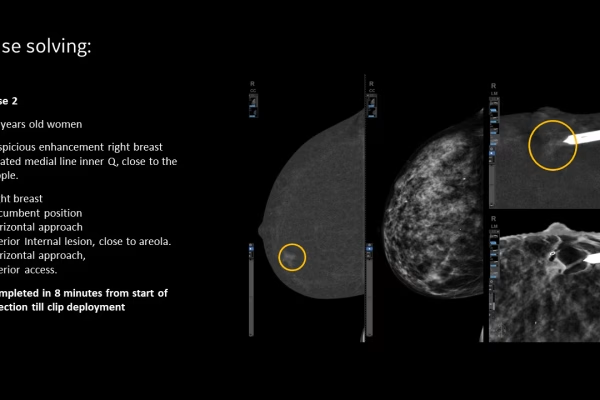

Mammographie GE Senographe